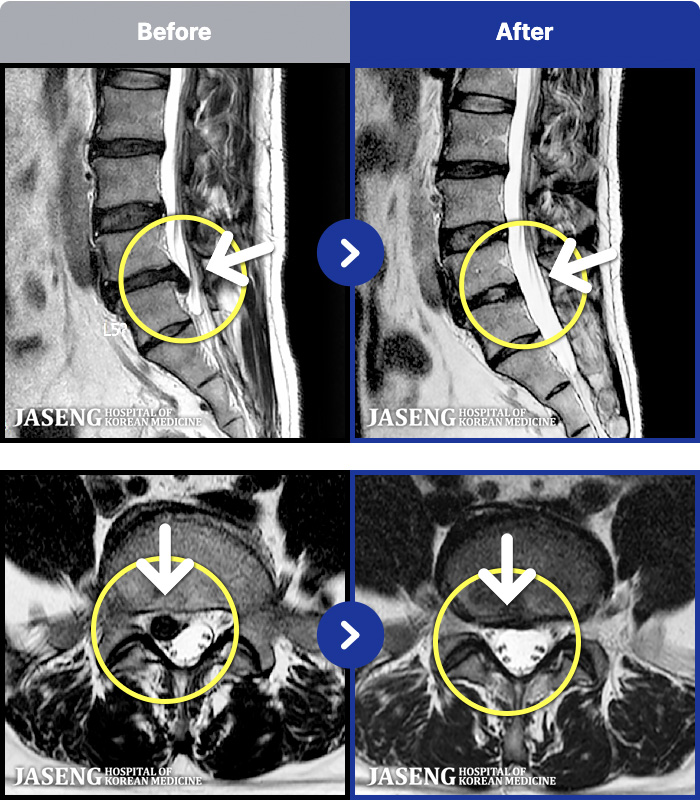

MRI ġ

1,237 MRI ũ ʸ Ȯϼ.